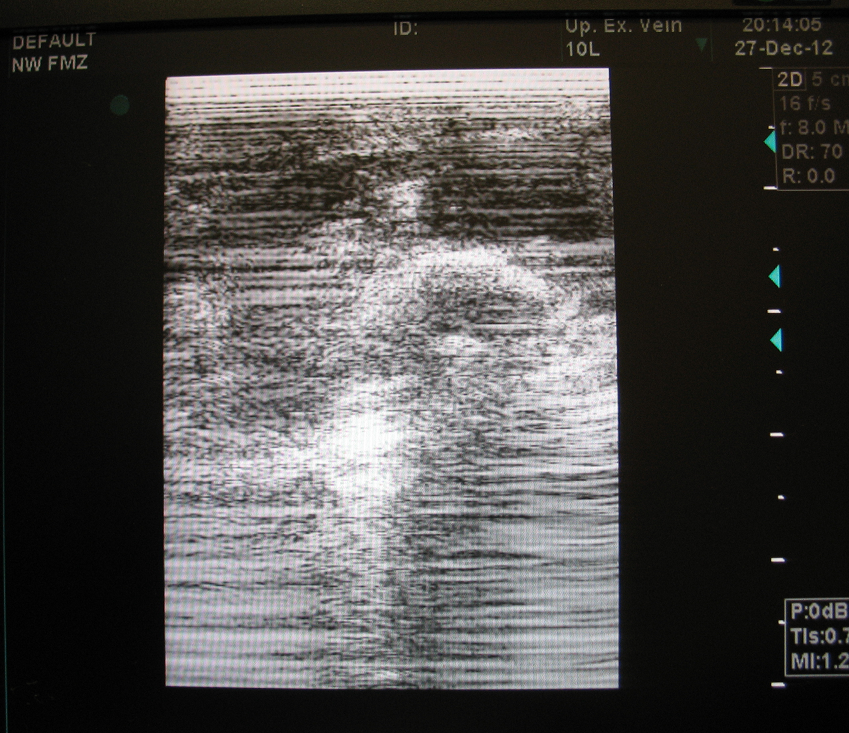

на цветном изображении возникают помехи(см.фото)если у кого-то была такая проблема-поделитесь.

Я склоняюсь больше всего к BF board илт RCT board

Судя по фоткам, первоначально я бы уделил внимание датчику, наличию (отсутствию) земли, и качеству питающей сети.

я пробовал другой датчик(с другого рабочего vivid3) и проблема была таже.

На счёт качества сети-аппарат имеет ON-LINE UPS.я пробовал аппарат и от других розеток-проблема таже.